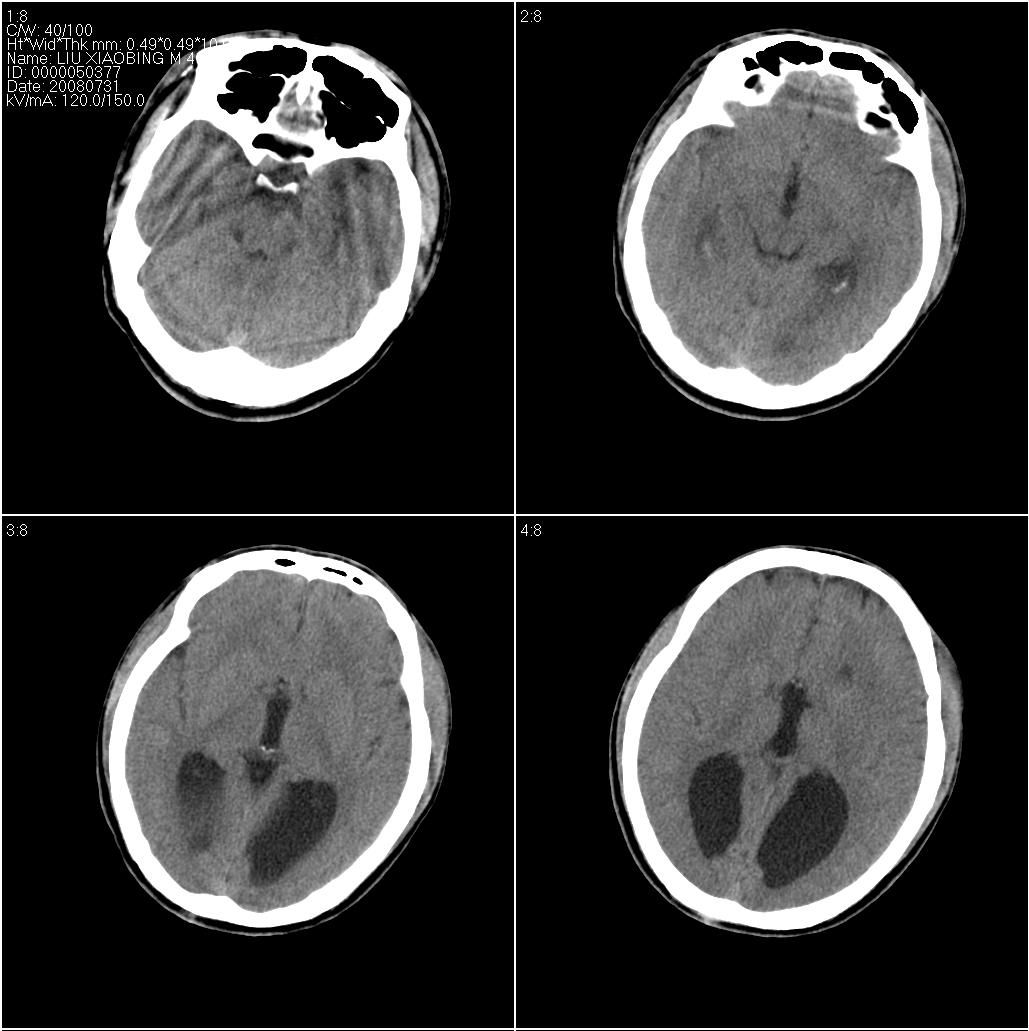

以下是引用牟言科在2008-8-11 20:00:00的发言:[br]ct表现:三脑室扩大并向上移位,双侧脑室体部变小、变直,体部间距扩大,枕角扩张,前纵裂向后延伸。[br]诊断:胼胝体发育不良[br]鉴别诊断:脑积水,侧脑室或三脑室整体扩大,交通性的四脑室也可以扩大,脑沟和脑裂增宽。